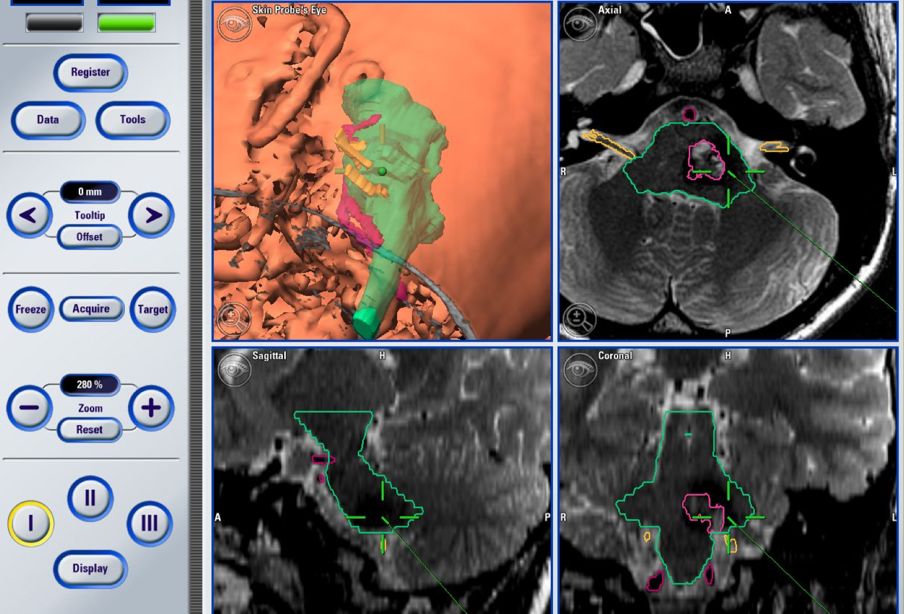

手术按计划实施。巴特朗菲教授选择乙状窦后入路,在高倍手术显微镜的辅助下,借助全程电生理监测技术精准定位脑干内部的神经核团,在明确病变与颅神经及脑干核团的毗邻关系后,历时约两个半小时,将病变组织完整切除,实现了手术目标。

但这一前提的成立,高度依赖主刀医生的经验积累与技术水平,同时离不开一整套先进辅助设备的配合支持:术中神经电生理监测、高精度术中导航系统、神经内镜以及高倍手术显微镜,这些构成了保障脑干手术安全的基本条件。